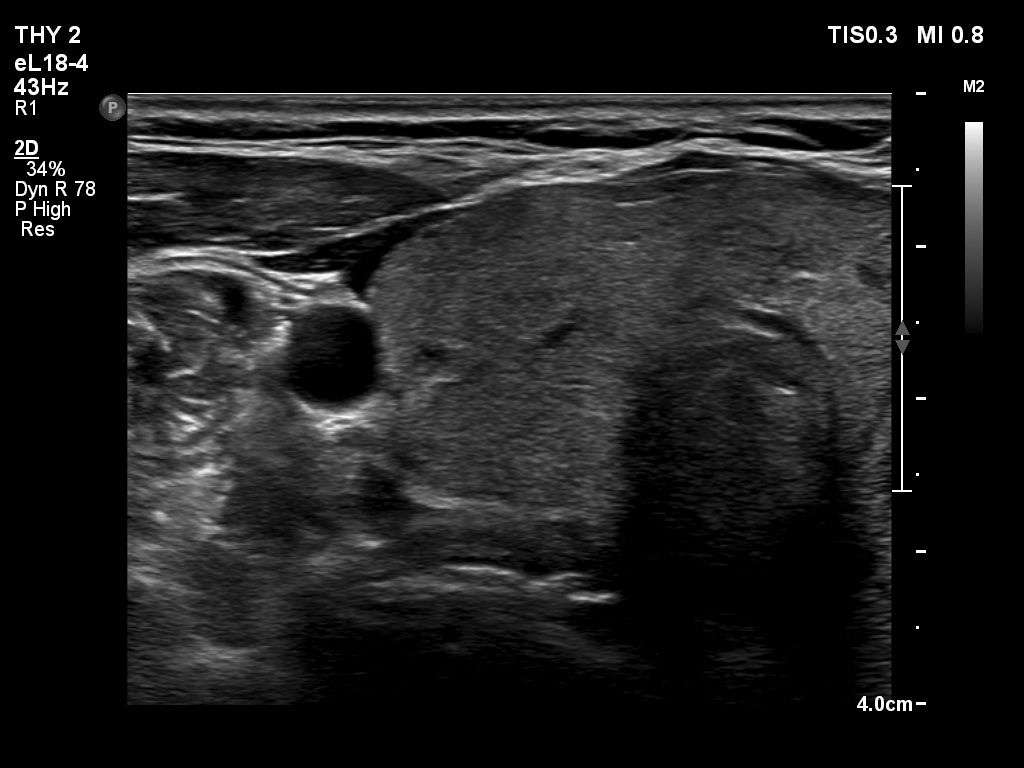

Right lobe, longitudinal scan

Right lobe, transverse scan. The thyroid is echonormal and has several discrete areas.